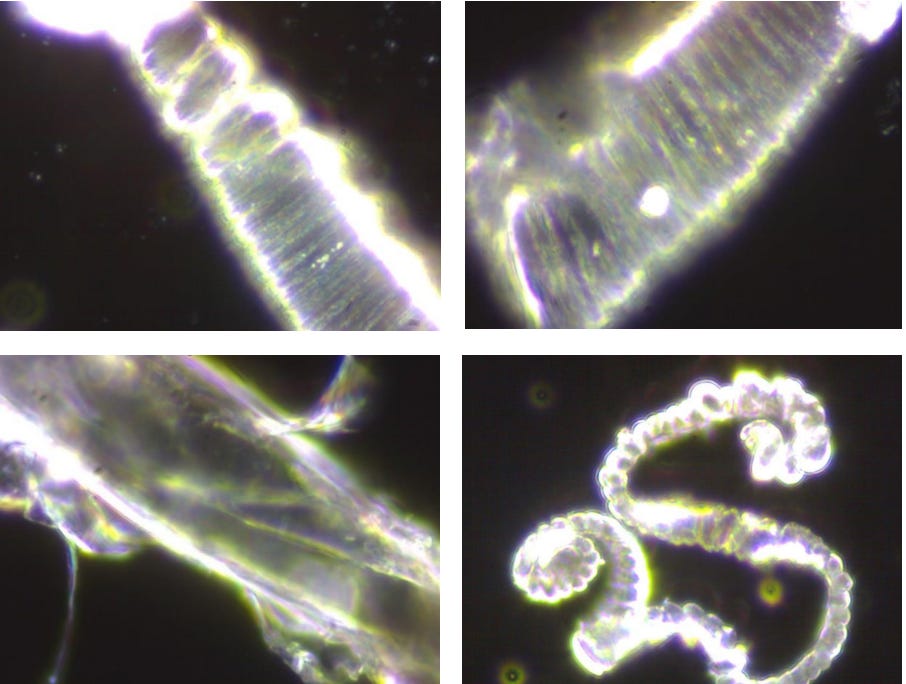

Estas 4 imágenes ilustran la variedad de fenómenos y objetos inusuales encontrados en la sangre de sujetos vacunados con Comirnaty BioNTech/Pfizer (Cortesía de Helen Krenn)MÁS

These substances, furthermore, “are visible under the dark-field microscope as distinctive and complex structures of different sizes, can only partially be explained as a result of crystallization or decomposition processes, [and] cannot be explained as contamination from the manufacturing process,” the researchers found.